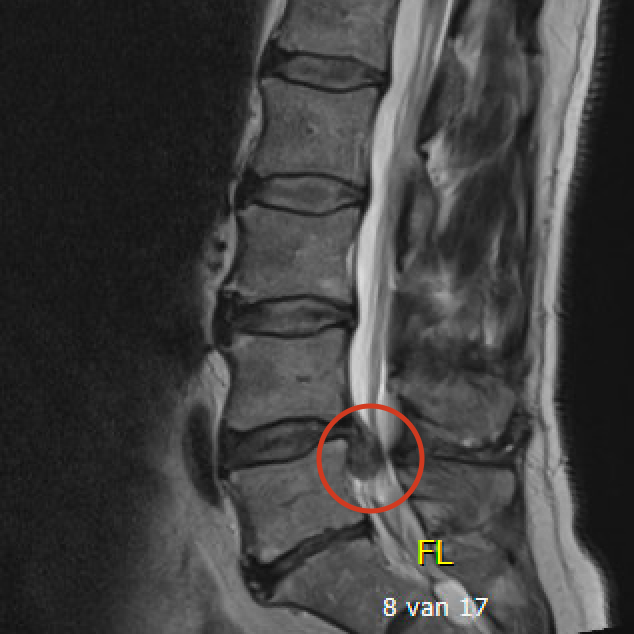

Discus hernia betekent in het Nederlands breuk (= hernia) van de tussenwervelschijf (= discus). Een tussenwervelschijf bestaat immers uit een centraal zacht gedeelte en een omliggende ring. De breuk ontstaat in de buitenste ring waardoor het zachte gedeelte naar achter schuift en druk geeft op het ruggenmerg of zenuwen. Hierdoor kan pijn in het been ontstaan (in de volksmond omschreven als ischias, sciatique of ingeklemde zenuw) wat het typische symptoom is van een hernia in de lage rug. Een hernia kan ook aanwezig zijn zonder symptomen en moet dan ook niet verder behandeld worden.

Het ideale onderzoek is een NMR (=MRI). Het levert ons de beste beelden en gebruikt geen nadelige X-stralen. Soms wordt ook een CT scan van de lumbale wervelzuil gevraagd.